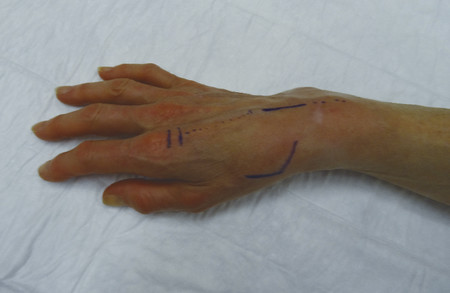

The patient shown in Fig. 9‑1 presented to the hand trauma clinic with an inability to extend the thumb. She had been managed conservatively in cast for 8 weeks for a distal radius fracture (Fig. 9‑2). Clinical examination confirmed a ruptured EPL tendon. An EIP to EPL transfer was performed under regional anesthetic (Fig. 9‑3, Fig. 9‑4, Fig. 9‑5, Fig. 9‑6, Fig. 9‑7). The EPL which lies in the third extensor compartment is thought to undergo ischemia due to edema which consequently results in tendon necrosis and rupture.

The patient is placed postoperatively in a forearm-based splint with the repair protected in a thumb spica extension cast. The plaster of Paris splint is changed to a thermoplastic splint on day 3 and early active mobilization is started. A protective splint must be worn for 12 weeks.